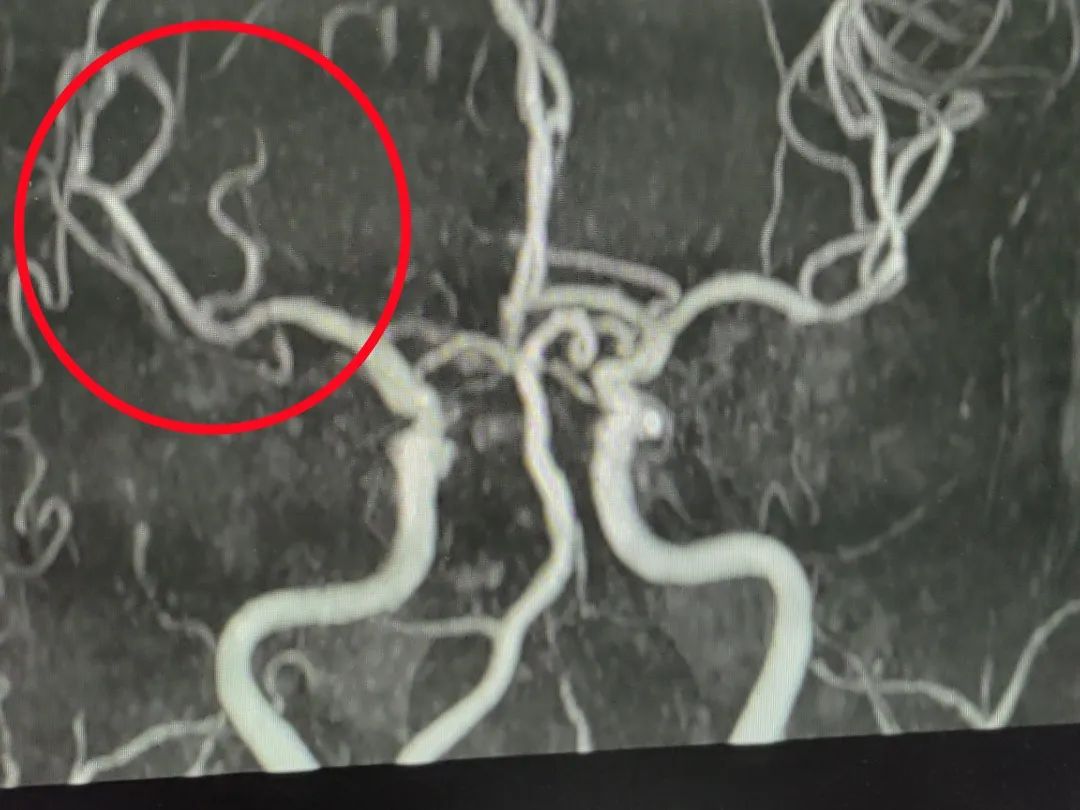

溶通前,红圈内为本次发生堵塞血管▲到达医院后,医生立即对老人进行了

图片尺寸900x675